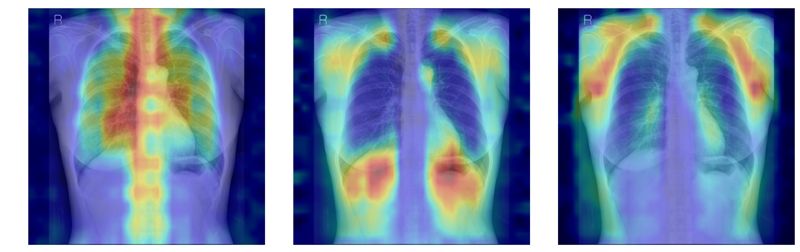

| 흉부X선에서 파운데이션 모델이 골다공증 판독을 위해 주목한 영역을 시각화한 이미지. 서울대병원 제공 |

‘차단 분석’은 모든 뼈 구조를 가린 뒤 특정 뼈를 순차적으로 노출했을 때 성능이 얼마나 향상하는지를 분석한다. ‘유의성 지도 분석’은 Grad-CAM으로 도출한 AI의 주목 영역이 실제 뼈 위치와 얼마나 일치하는지를 평가한다.

이를 통해 AI가 임상적으로 중요한 척추·늑골을 중심으로 예측 근거를 삼고 있음을 확인했다. 단순히 ‘정확도가 높은 모델’이 아니라 판단 근거가 의학적으로 타당한 모델임을 입증한 것이다.